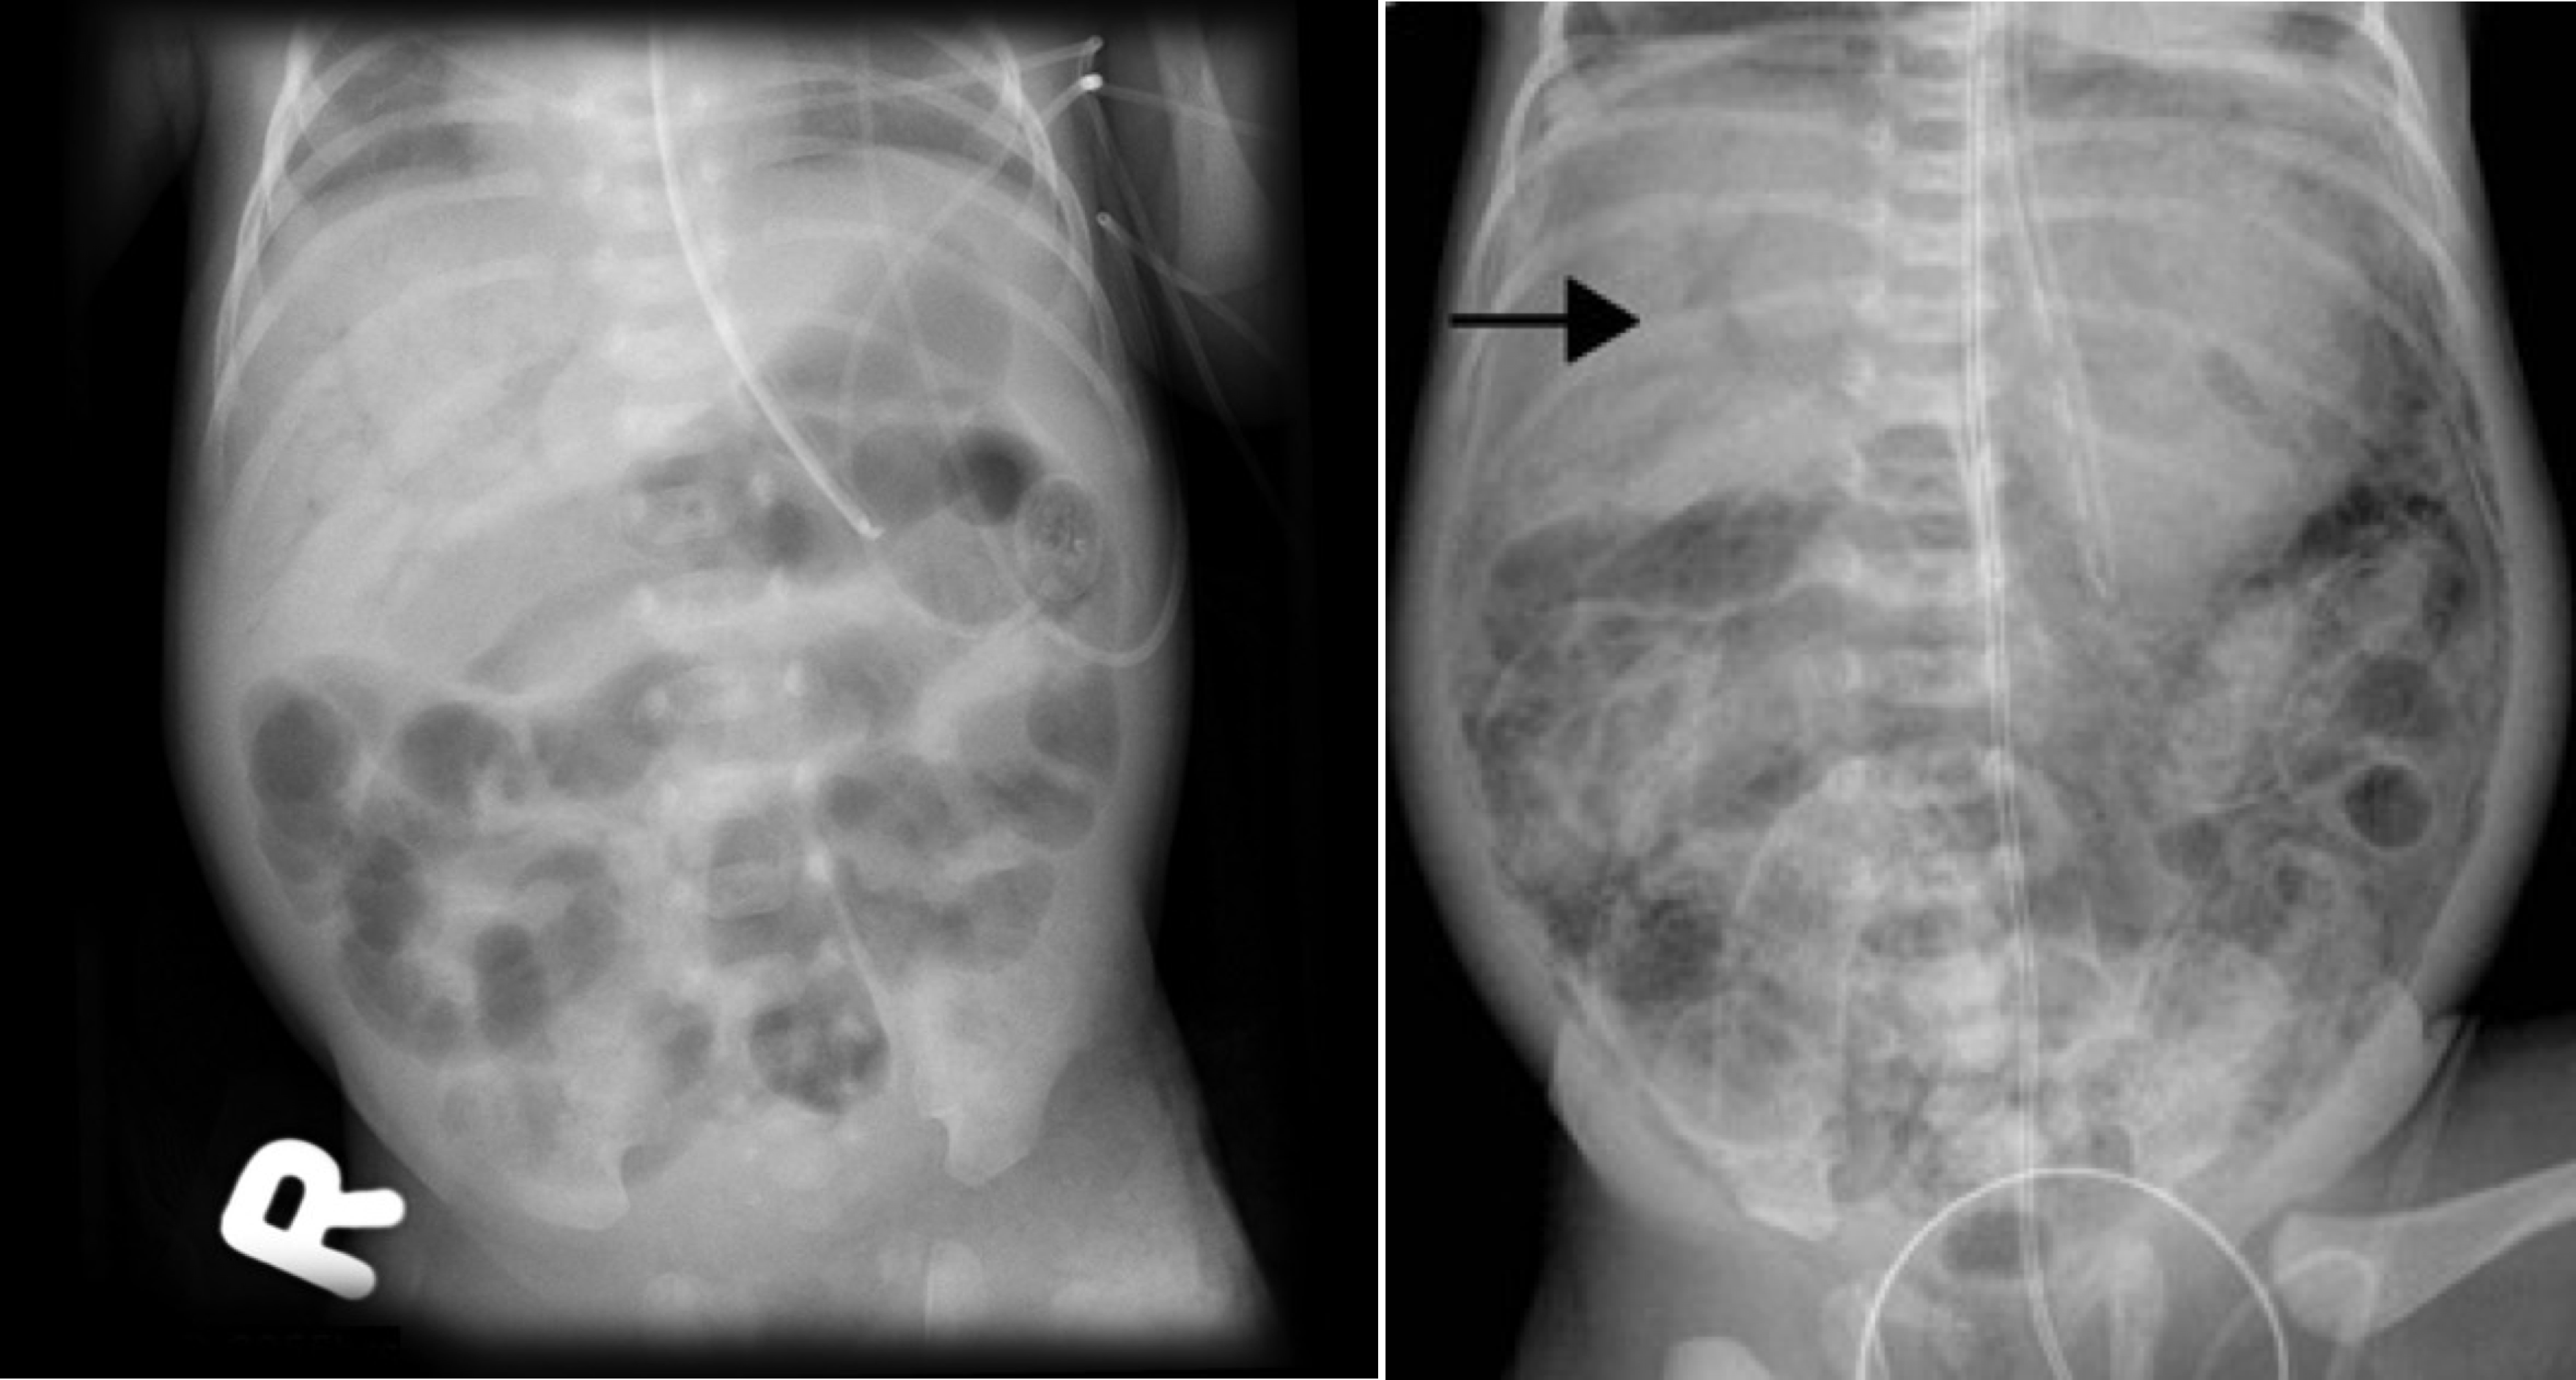

• pneumatosis intestinalis (intramural bowel gas)

: 방사선 검사 상 장 벽 내부에 공기음영이 보이는 소견 (장벽의 괴사를 시사)

• portal vein gas

:NEC가 진행되면 장벽 내의 가스가 혈관으로 들어가 간문맥을 따라 공기음영이 확인